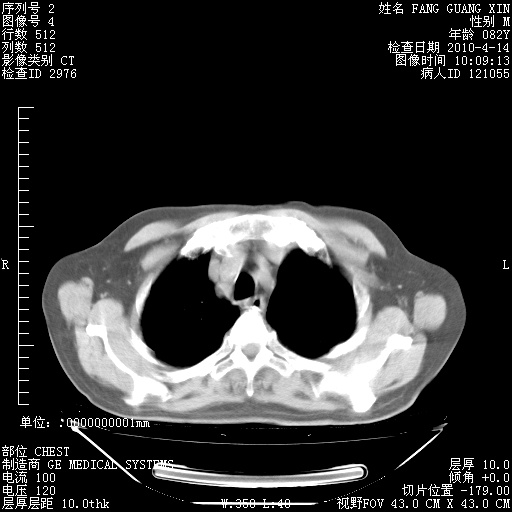

4月14日肺部CT